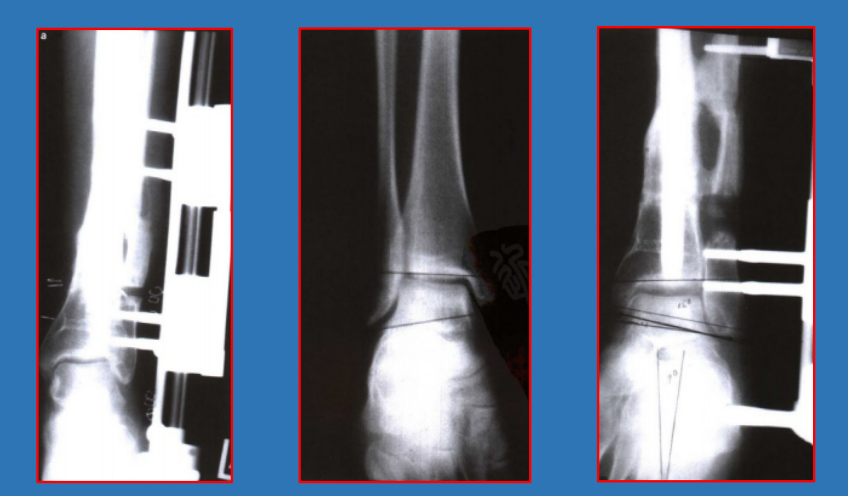

腓骨短缩测量

胫距角talocrural angle:通过在踝穴位X线片上测量内、外踝尖端连线与胫骨远端关节面平行线的夹角。正常值为8~15°,与健侧相差3°以上即表示有腓骨短缩。

三角韧带损伤

内踝间隙medial clear space如果在前后位或踝穴位X线片上测得内踝与距骨的间隙(medialclear space)大于4mm,无论X线片是否是在应力下拍摄,都表示有三角韧带的损伤

下胫腓联合分离

胫腓间隙、重叠,胫腓间隙在前后位上大于6mm或胫腓重叠在前后位上小于6mm、在踝穴位上小于1mm,即表示存在下胫腓联合的分离。

踝穴宽度 D线在距骨关节面下方5mm处,平 行于距骨关节面,与胫骨、腓骨相 交于a、b、c、d四个点 、踝穴宽度=ab-cd 、正常范围2~6mm。

在旋后外旋SER类型中:内踝间隙>4.5mm、骨折高度>7mm